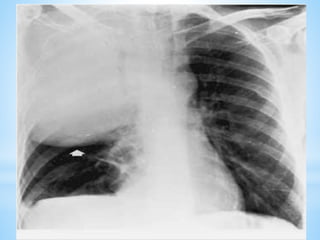

2.1.2. Signes radiologiques

a) Radiographie thorax (face +/- profil)

Doit être réalisée systématiquement

*De profil: topographie exacte de l’opacité

*Nota bene

*peut être normale (les 1ères heures)

*ne peut à elle seule permettre le diagnostic

bactériologique

*au cours de l’évolution, signes radiologiques

sont en retard par rapport à la clinique.